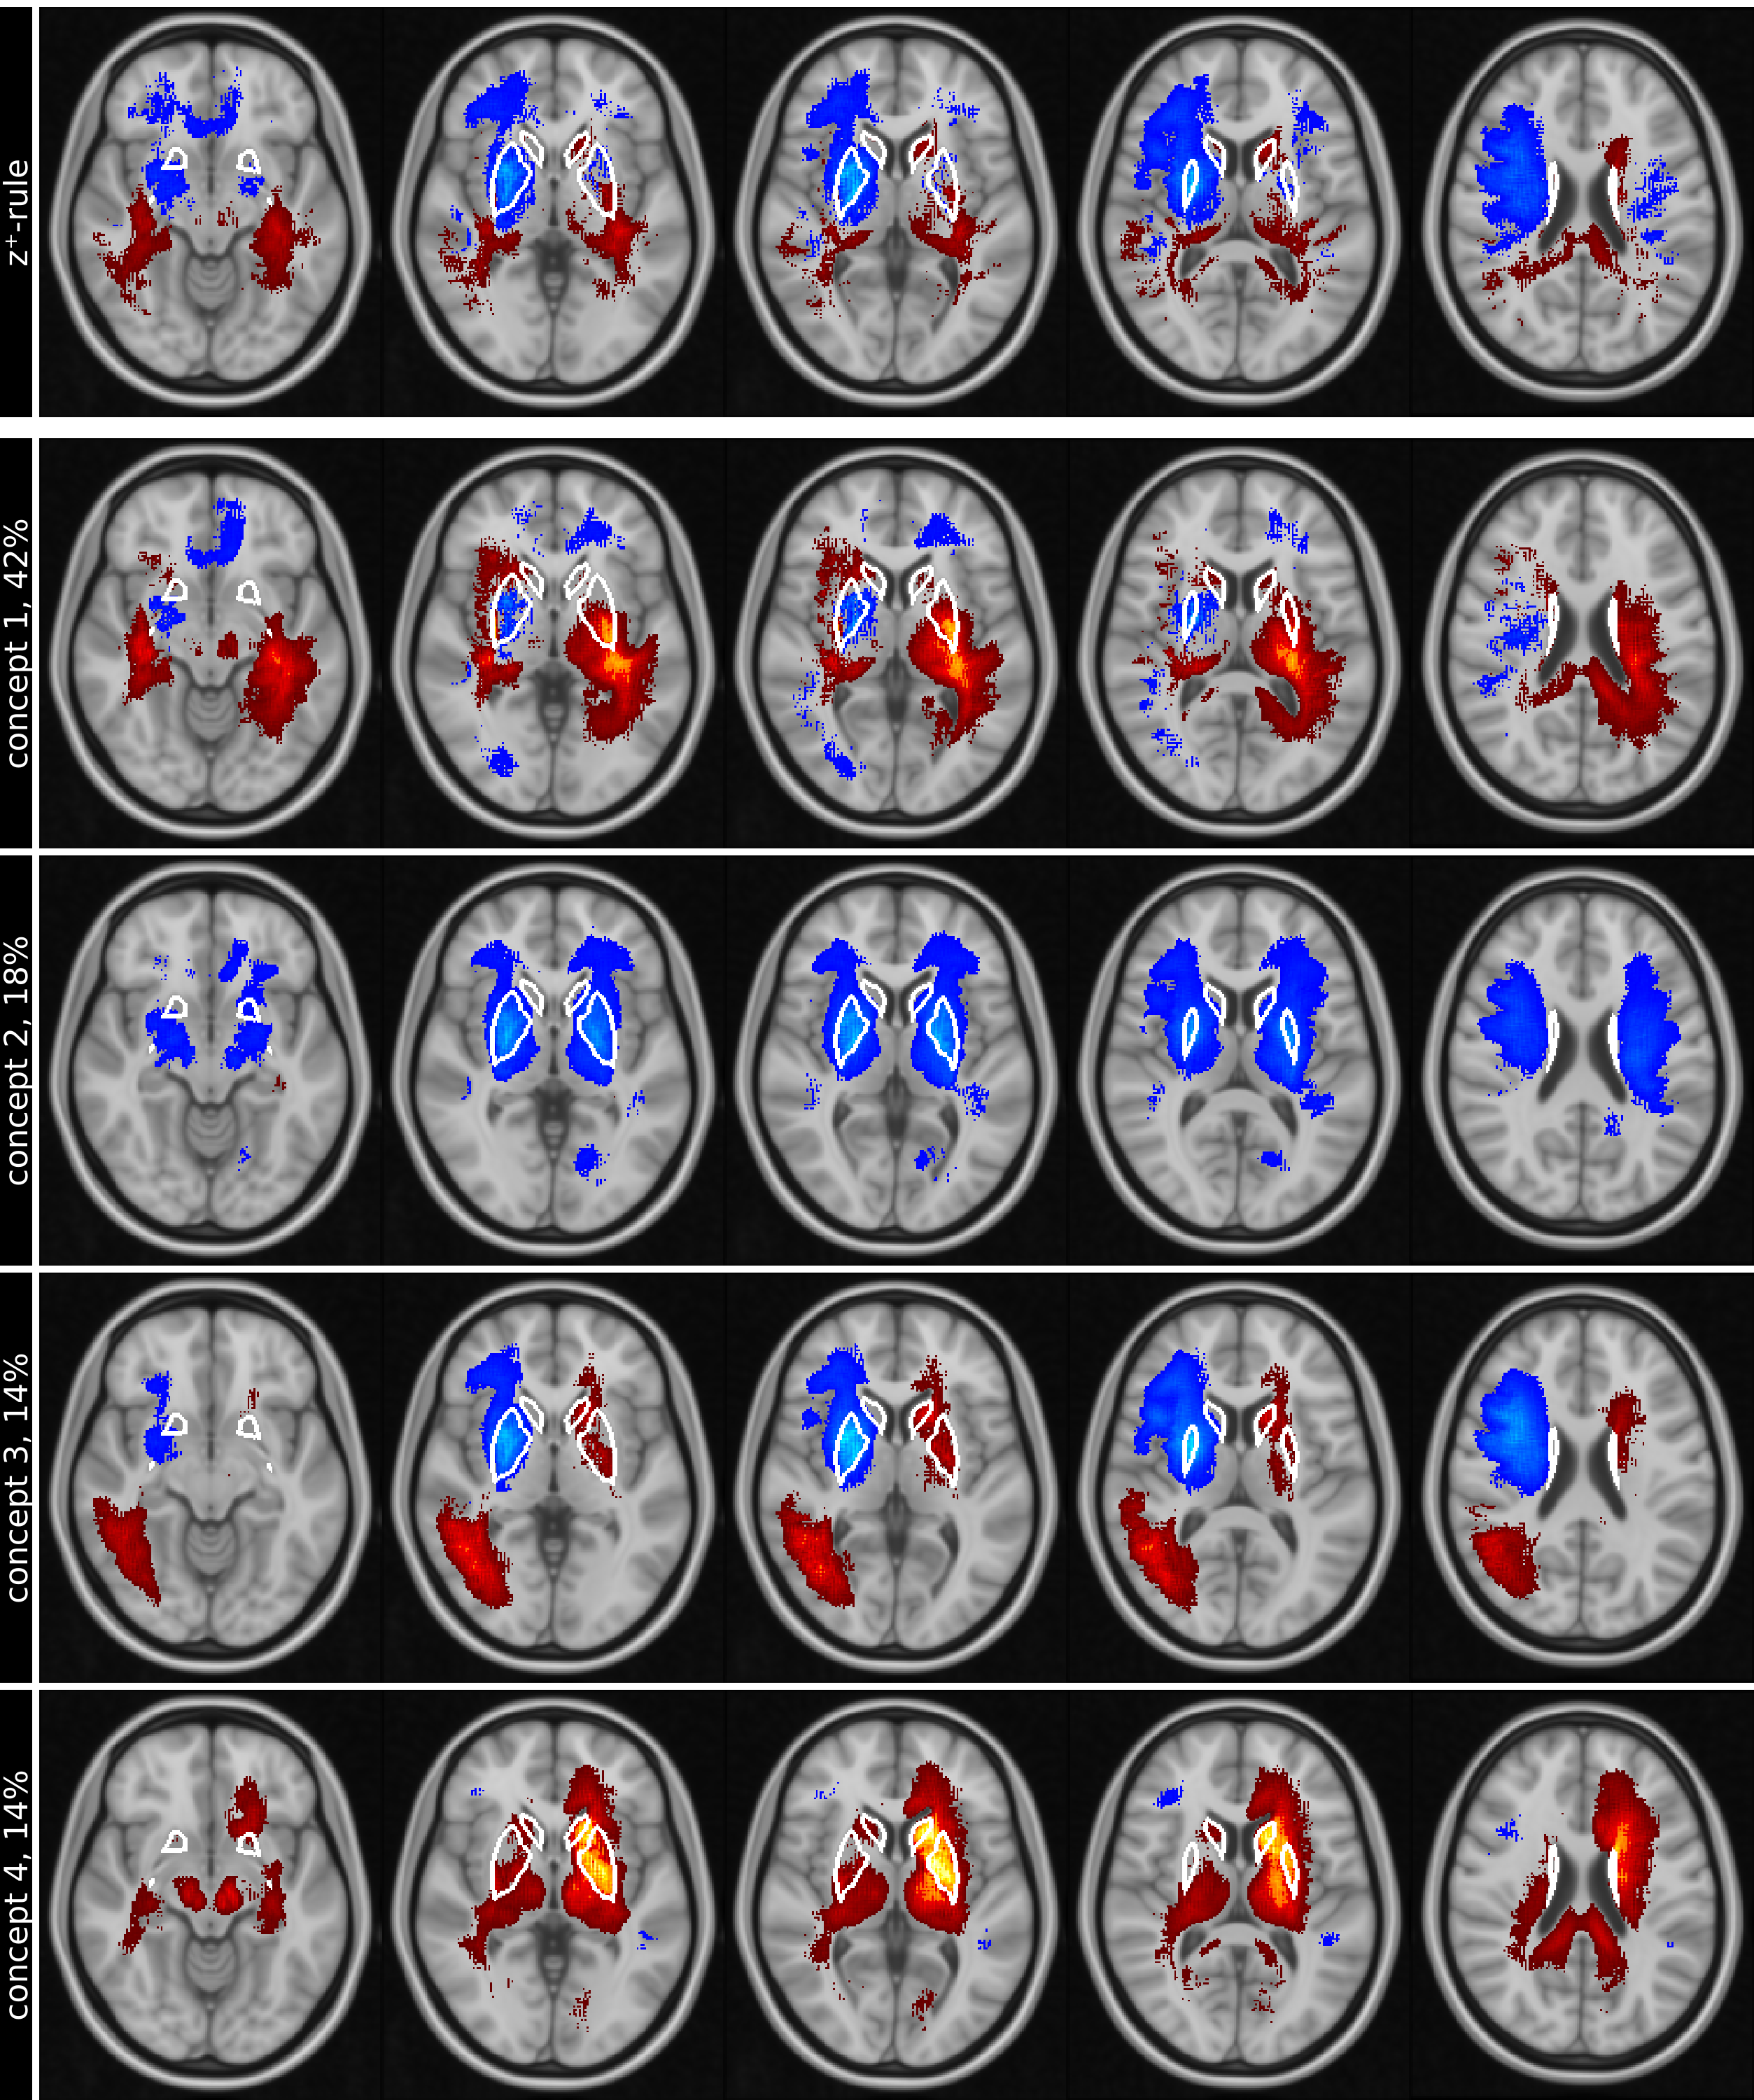

The differences between the concept attribution for AD and NC classification of the best-performing bootstrapping run are shown in Figure 2. Additionally, Table 1 shows the relevance sum in the basal ganglia for the four most important concepts and the results of the tests for differences in the classes. The base images for computing the differences in concepts between AD and NC are shown in Figure 4 and Figure 5 in the Appendix.

Qualitatively, concept maps differences show a substantial overlap with the basal ganglia regions. The median R2* values in selected anatomical brain regions are given in Table 2.

Refer to caption

Figure 2: Row (1) shows the difference of conventional mean global heat maps created for AD and NC using LRP-z+superscript𝑧z^{+}-rule for five slices (columns), overlaid on the MNI152 standard-brain 1mm template. In comparison, rows (2) to (5) show the differences of the four most important concepts on the same slices, ranked by their relative importance (percentage next to name) for the classification results. Negative differences are presented as blue-lightblue and indicate regions in concepts with more attribution in AD compared to NC, whereas positive differences, shown as red-yellow, highlight regions in concepts with more attribution in NC compared to AD. If the attribution in NC and AD is similar (e.g. concept is nearly equally used for both classes) the regions disappear. Images are shown in standard-radiological view, thus left and right is flipped and white lines outline the basal ganglia.

Therefore, this study identified the concepts of the CNN-based classification with R2* maps. Various studies have shown that brain iron increasingly accumulates in the deep gray matter of AD patients [6, 13]. While the highest relevances in and adjacent to the basal ganglia are consistently involved in all concepts, differences in concept mapping identified complementary spatial patterns (e.g. concept 1 and concept 3, Figure 2).

The differences in concept 1 show substantial positive differences in and adjacent to the left basal ganglia, whereas the right basal ganglia show nearly no differences. This was confirmed by the tests for relevance sum differences in Table 1 and was also found in susceptibility sensitive imaging in AD [6, 2]. Concept 1 seems to activate more for NC images, favoring smaller R2* values in the left pallidum, left putamen and left white matter, whereas concept 2 shows only negative differences, favoring higher R2* values in the left and right basal ganglia. Additionally, concept 3 shows positive differences in the right temporal and occipital lobes, which is in line with the analysis in [6]. Please note that all MR images in this paper are shown in standard-radiological view, causing the left and right side of the brain to be flipped.